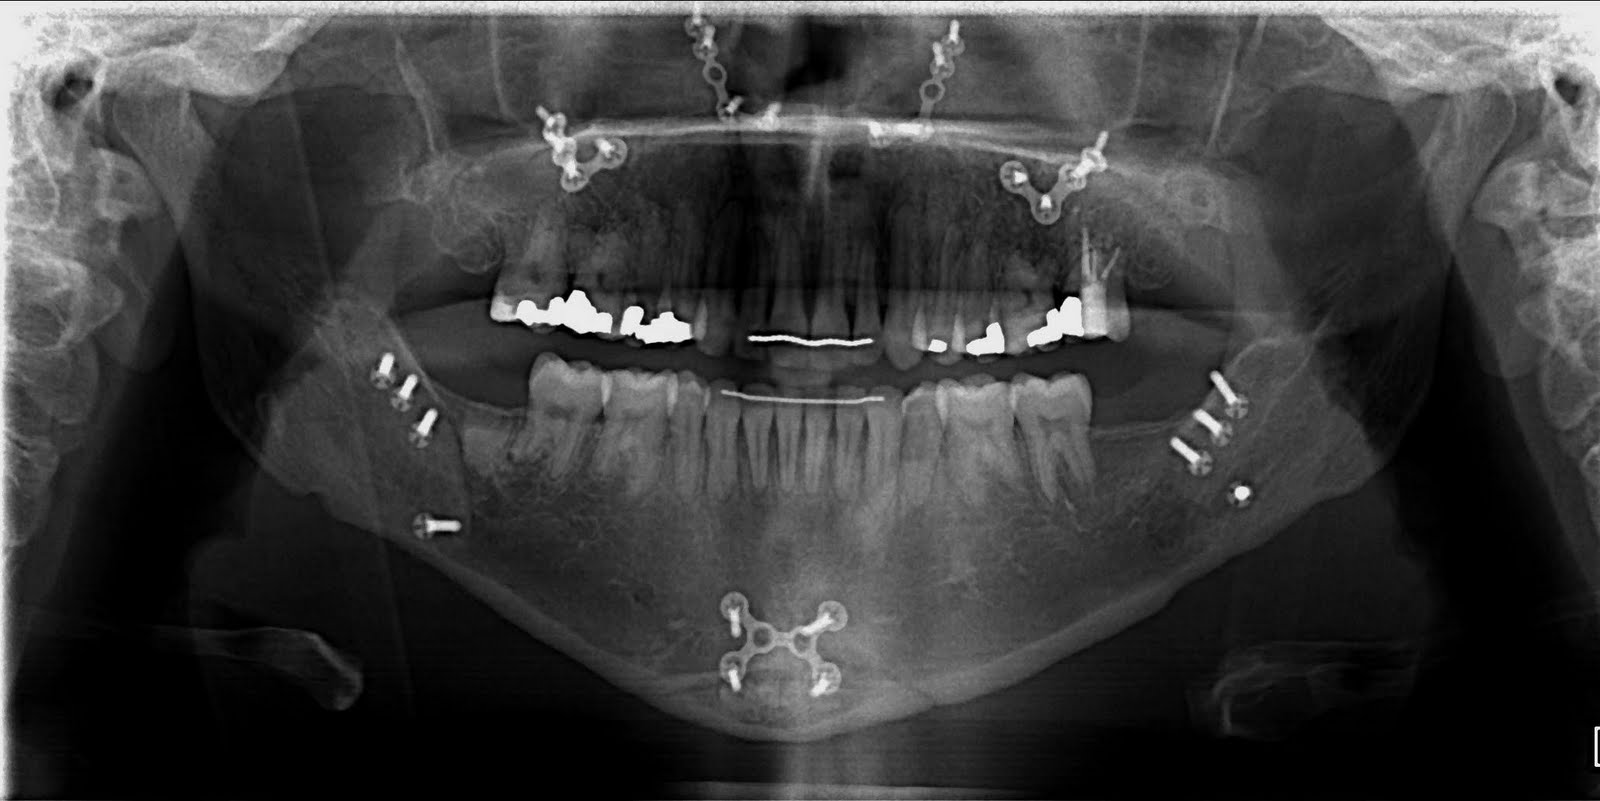

My Before & After XRays Jaw Surgery for mandibular advancement r/pics

XRay of total TMJ replacement and upper jaw surgery. jawsurgery Jaw Surgery Xray The plates or bars hold the bone in. Photo courtesy of lisa chan,. Proper characterization of jaw abnormalities is essential to ensure appropriate patient care and reduce morbidity. Imaging plays a key role in the characterization of a variety of jaw lesions, and radiologists must be familiar with these imaging findings. Your provider may do surgery, putting metal plates or. Jaw Surgery Xray.